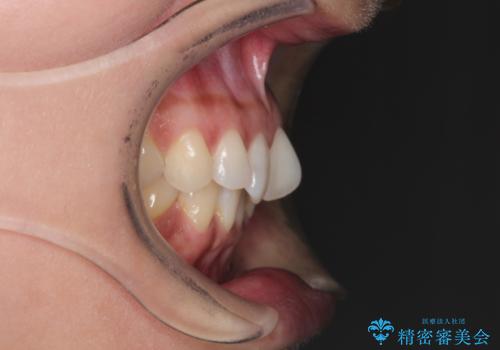

- 上顎の前歯のがたつきと、下の前歯の隙間を主訴に来院されました。

下の前歯が先天的に欠損していました。

上顎の歯と歯の間をわずかに削りスペースを作り、ガタガタの改善し、下顎の前歯は隙間を閉じる計画としました。